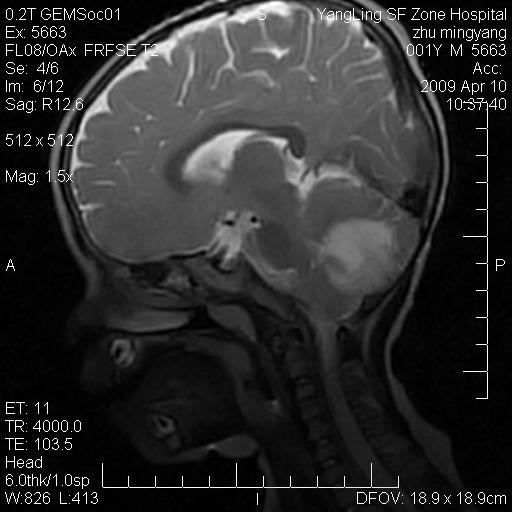

患者:1岁半,两天前外伤收住我院,ct检查小脑占位

考虑星形细胞瘤,建议增强

髓母细胞瘤或血管母细胞瘤,增强后可以鉴别;影像资料见 <。鱼博浪老师的《中枢神经系统ct与mr鉴别诊断》 小脑部肿瘤章节。

髓母细胞瘤或血管母细胞瘤!支持!

支持考虑髓母细胞瘤

考虑----髓母细胞瘤可能性大

考虑髓母细胞瘤或室管膜瘤。

支持髓母细胞瘤。

考虑髓母细胞瘤。

考虑髓母细胞瘤或星形细胞瘤

考虑髓母细胞瘤.

考虑髓母细胞瘤可能性大。

小脑肿瘤.考虑髓母细胞瘤可能.

就病灶部位及临床资料首先考虑髓母.